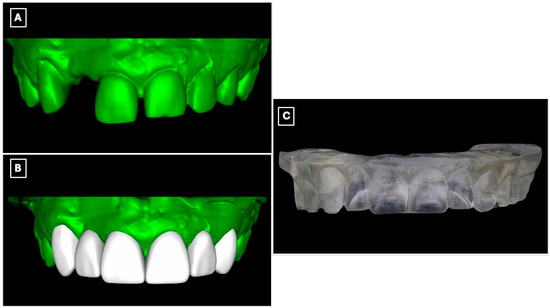

Diagnostic records were obtained, including preliminary impressions, and diagnostic casts were fabricated. The casts were digitized using an intraoral scanner (Medit i700, Medit Corp., Seoul, Republic of Korea) to enable a fully digital workflow (Figure 2A). A digital wax-up was subsequently designed based on esthetic, functional, and occlusal parameters (Figure 2B), allowing three-dimensional evaluation of tooth proportions, pontic position, and incisal edge relationships relevant to a minimally invasive adhesive prosthetic approach. The approved digital wax-up was then fabricated using a three-dimensional printer (NextDent 5100, NextDent B.V., Soesterberg, The Netherlands) to produce a physical diagnostic model for clinical reference and transfer of the digital plan to the operative phase (Figure 2C).

Figure 2.

Digital workflow used for diagnostic evaluation and prosthetic planning of the maxillary anterior region. (A) Digitized diagnostic cast obtained from preliminary impressions, allowing three-dimensional assessment of tooth position, edentulous space morphology, and enamel contours relevant to adhesive prosthesis design. (B) Virtual model following digital processing and wax-up, illustrating the planned tooth proportions, pontic position, and incisal edge relationships used to guide minimally invasive tooth preparation and prosthesis design. (C) Three-dimensionally printed diagnostic cast derived from the digital wax-up, used as a physical reference for mock-up fabrication and to facilitate accurate transfer of the digital plan to the clinical setting.